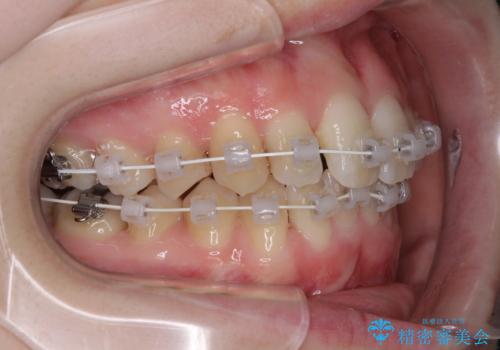

- 急速拡大装置・審美装置

急速拡大装置により上顎骨を側方に拡大し、ワイヤー装置により歯列を整えることとしました。

左右ともに奥歯の咬み合わせには大きな問題がなく、窮屈な歯列を解決すれば歯列を整えることできたため、僅か1年で終えることができました。